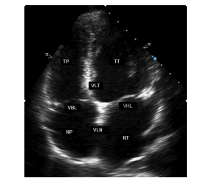

5.1.1. Cắt ngang thất

Thiết đồ cạnh ức trái (trục dài và ngắn) là vị trí chuẩn nhất để đo đạc các kích thước của TT trên siêu âm TM (theo phương pháp của Hội siêu âm Tim mạch Hoa kỳ)

Cắt ngang thất trái ngay sát bờ tự do của van hai lá, từ trước ra sau để thấy các cấu trúc: Thành ngực phía trước, thành trước của thất phải, buồng thất phải, vách liên thất, buồng thất trái, thành sau thất trái, thượng tâm mạc dính vào ngoại tâm mạc cho hình ảnh siêu âm đậm.

Hình 1: Hình ảnh siêu âm TM cắt ngang thất trái.

Các thông số cần đo trên mặt cắt này:

* Vào cuối thời kỳ tâm trương (khởi đầu sóng Q của phức bộ QRS trên ĐTĐ)

- Đường kính thất phải.

- Bề dày VLT.

- Đường kính thất trái.

- Bề dày TSTT.

* Vào cuối thời kỳ tâm thu (đo ở vị trí VLT đạt được độ dày tối đa)

- Bề dày VLT và TSTT.